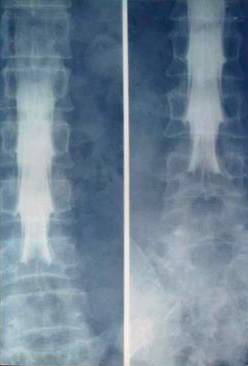

1、X线平片:根据脊柱屈度、椎间隙等变化,可间接推断椎间盘突出。

X线:脊柱侧弯,屈度较柔和

腰椎生理弯曲消失